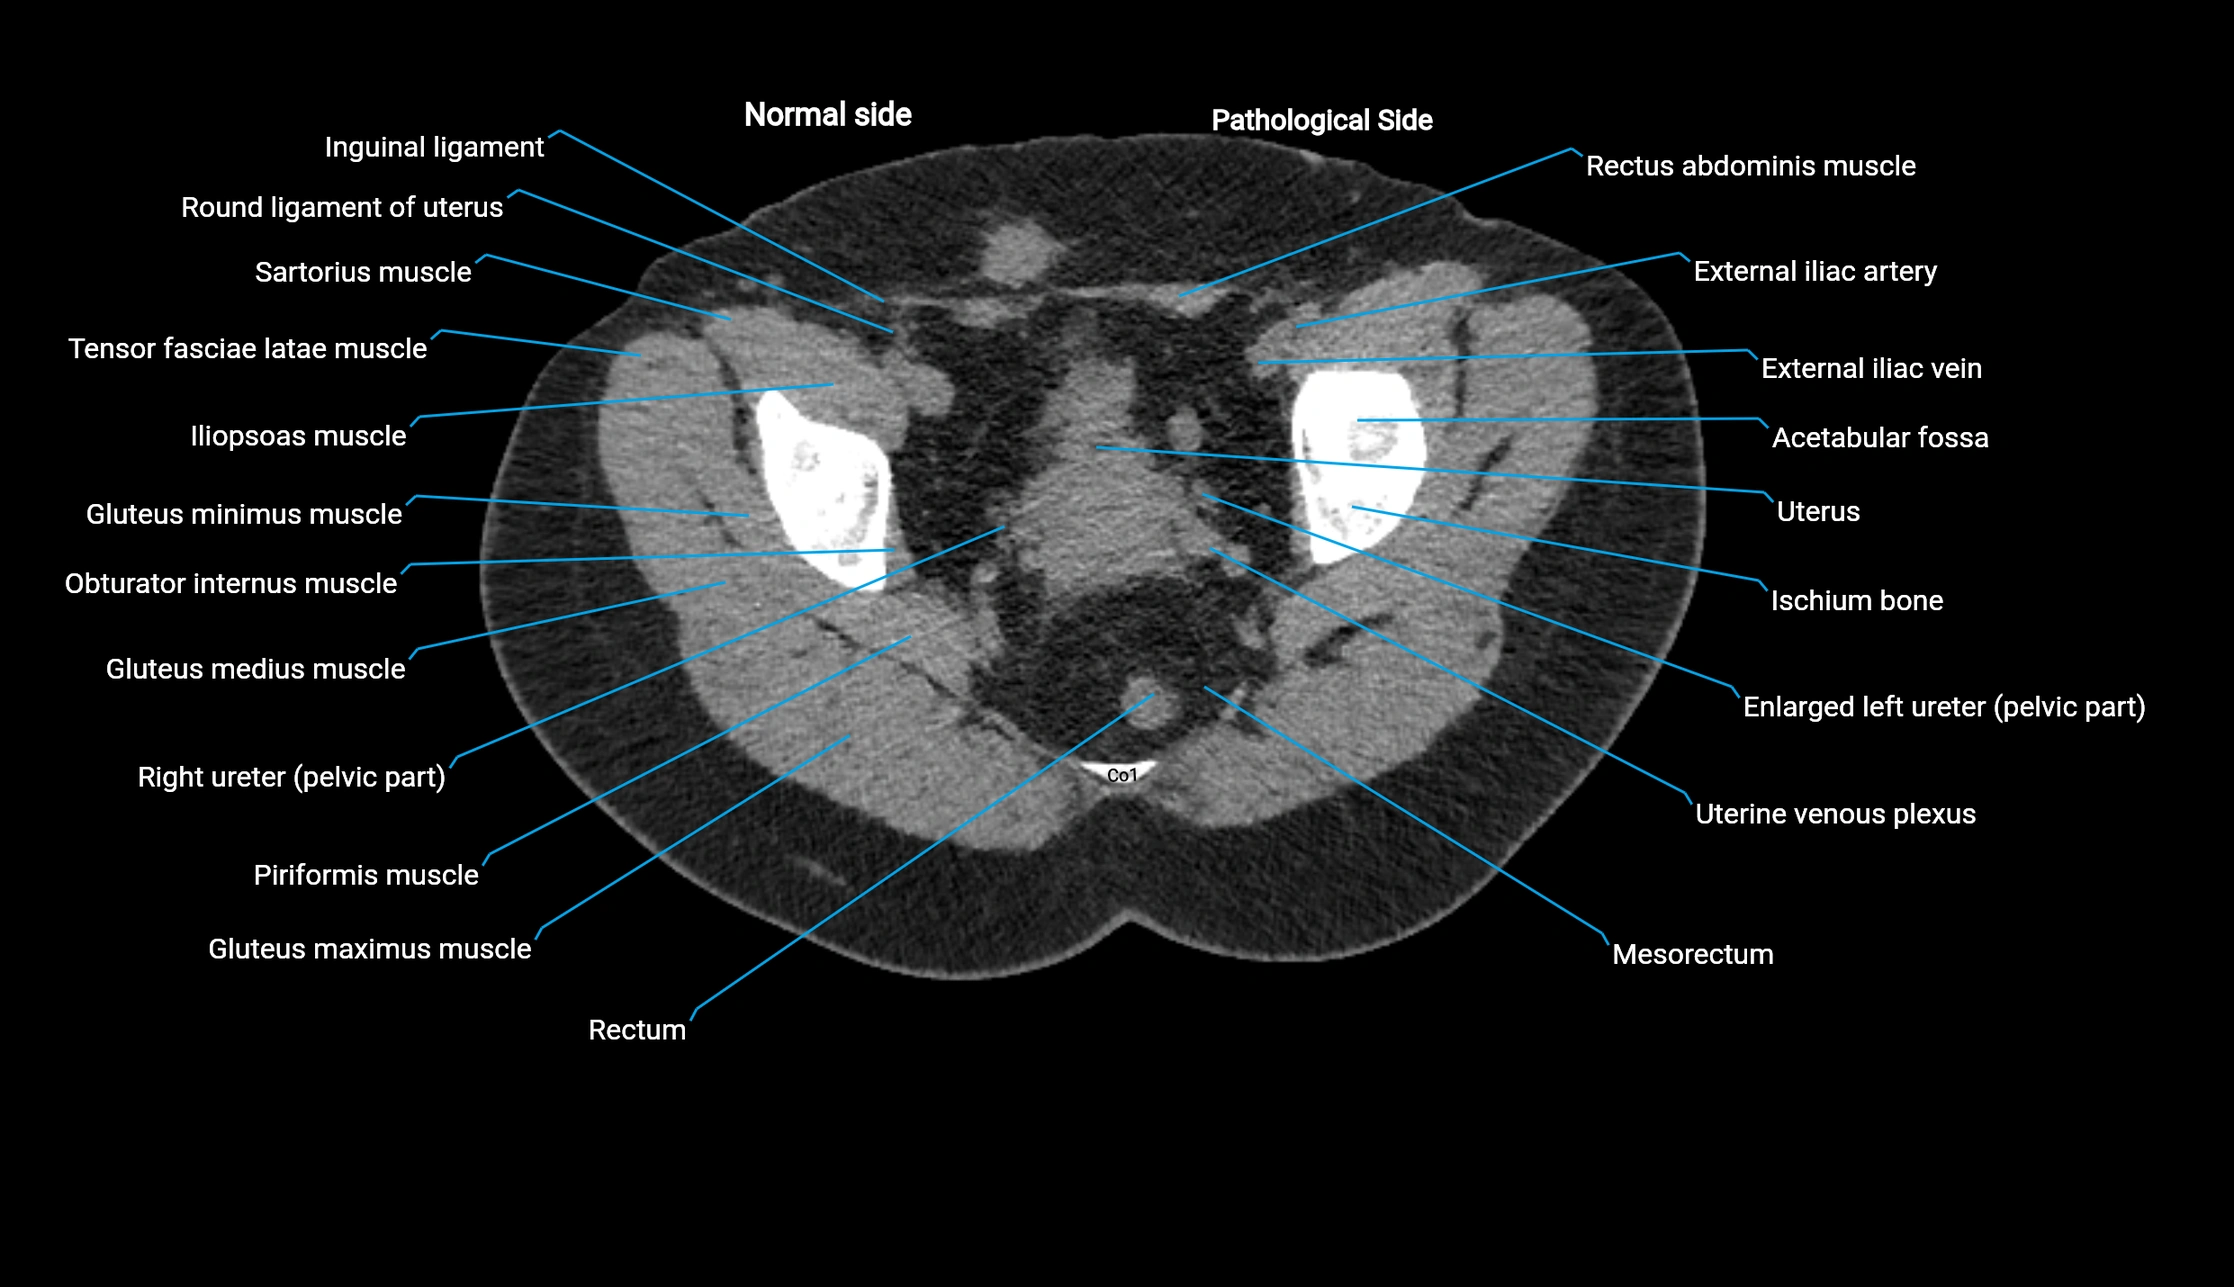

CT image

image